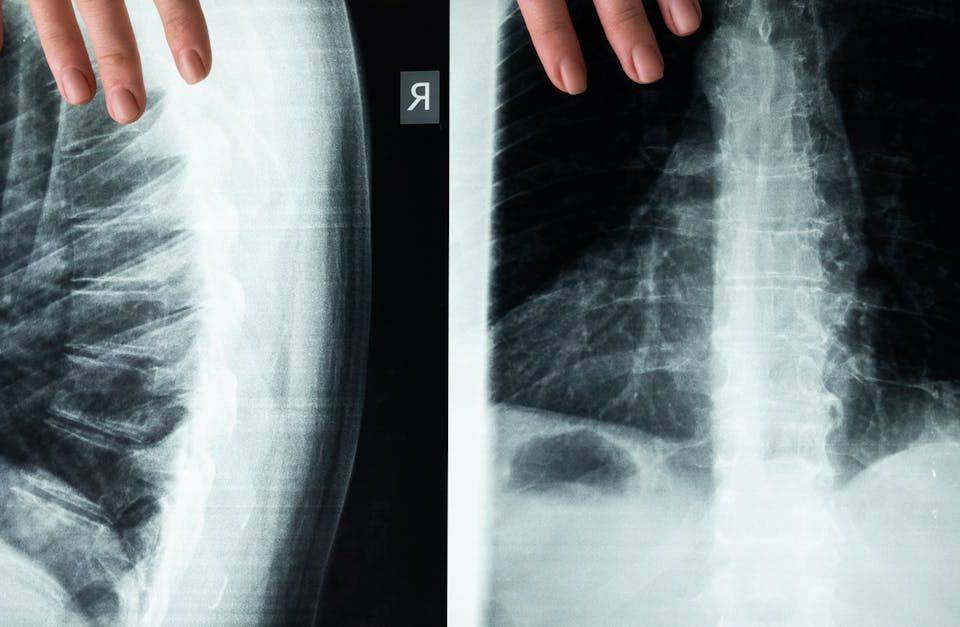

Les étapes pour établir un diagnostic précis de sténose spinale avant de commencer un traitement

EN BREF En résumé, la sténose spinale est un rétrécissement du canal rachidien qui peut entraîner des douleurs et des problèmes de mobilité. Le processus de […]